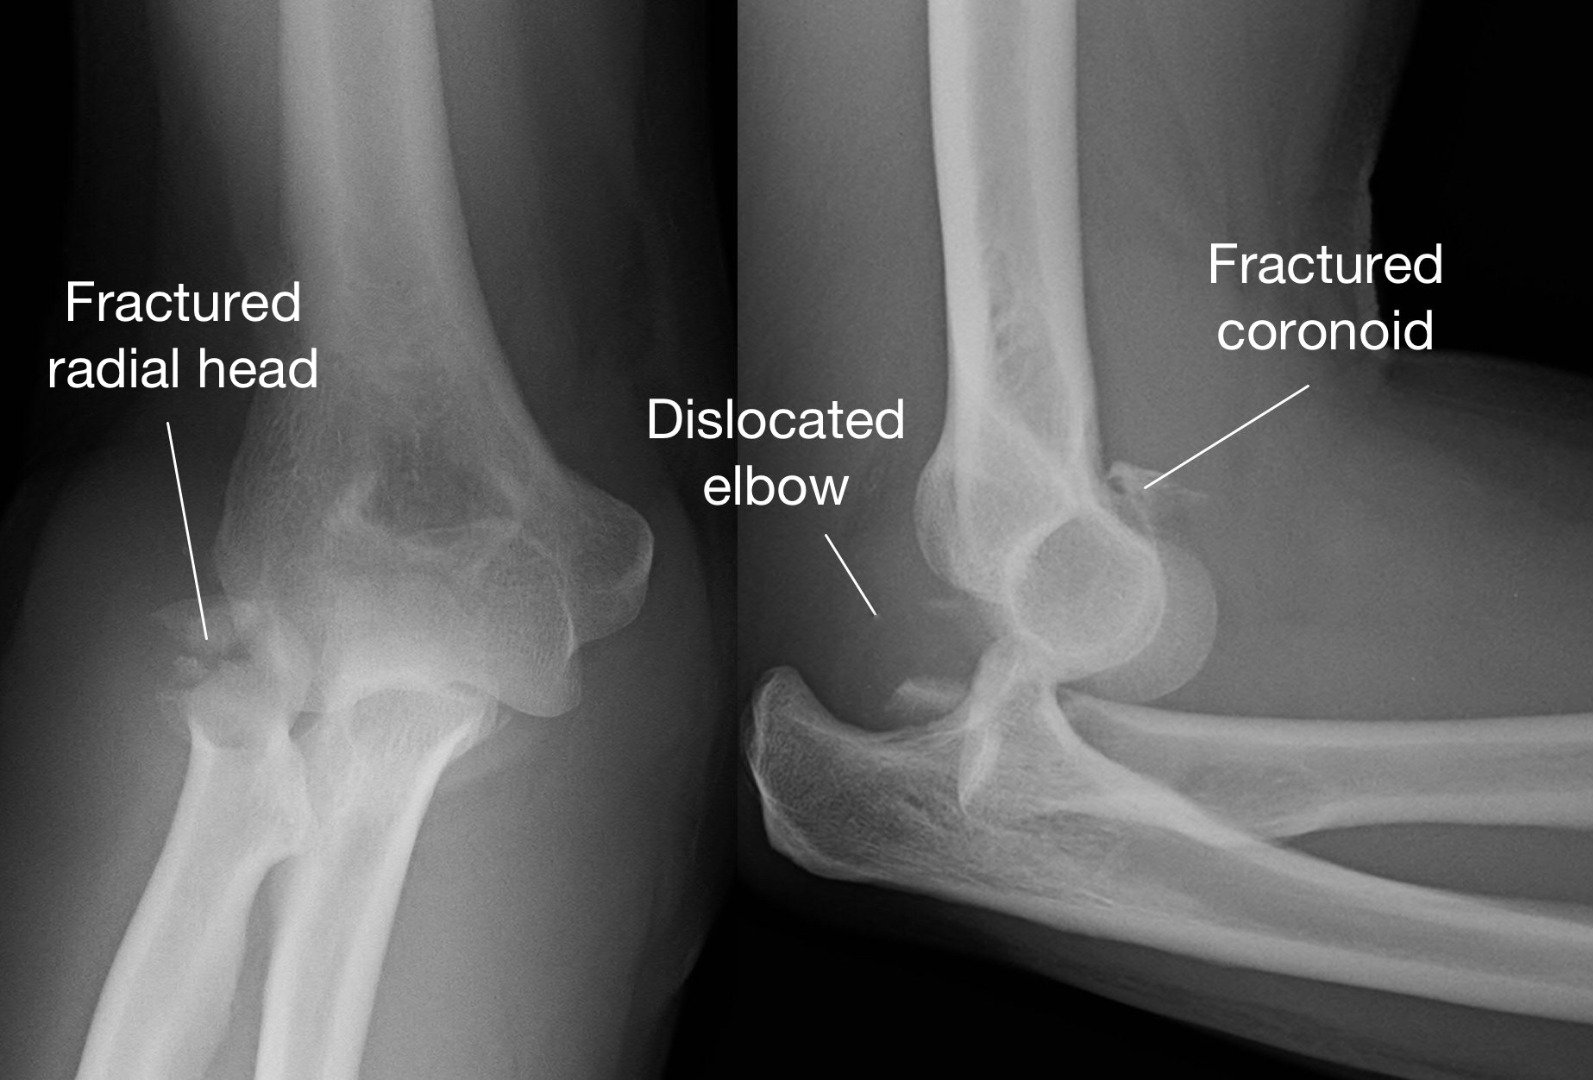

Discover effective treatment for sore elbow tendons with our expert guide. Learn how to manage tennis elbow and golfer’s elbow through proven physical therapy exercises, anti-inflammatory remedies, and ergonomic adjustments. Relieve chronic joint pain, reduce inflammation, and accelerate your recovery process with these practical, science-backed strategies designed to restore mobility and strengthen your arm tendons today.